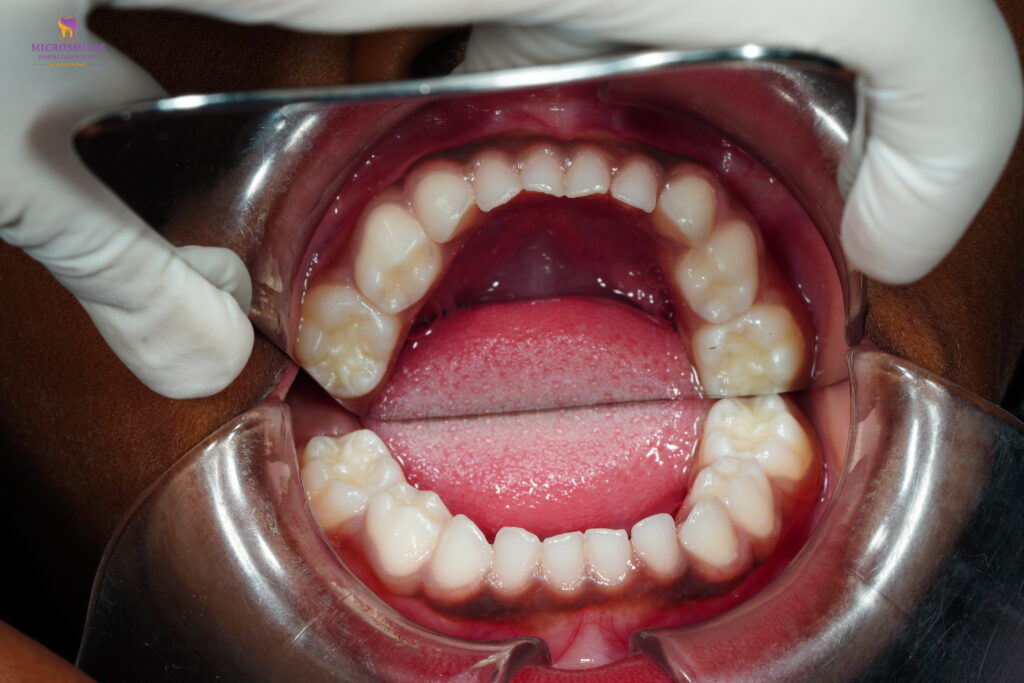

Pulp therapy is often called a “baby tooth root canal.” It involves removing the infected or inflamed part of the nerve (pulp) while preserving the rest of the tooth. It’s typically followed by a protective crown-allowing your child to chew, speak, and smile pain-free.

After pulp therapy, we usually place a protective cap (like a stainless steel or zirconia crown) to reinforce the tooth and prevent further damage. Your child can return to regular eating and brushing the same day in most cases.